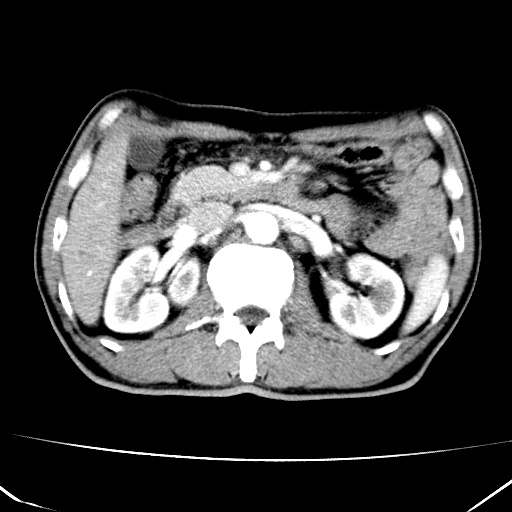

标题: CT17975:请求会诊。男、57岁。上腹部胀痛2天。临床诊断:糜 [打印本页]

标题: CT17975:请求会诊。男、57岁。上腹部胀痛2天。临床诊断:糜

肝脏多发类圆形低密度影,考虑肝脏转移瘤,肝胃韧带一淋巴结肿大,原发?胃癌?

考虑胃癌并肝脏及腹膜后淋巴结转移;不排除淋巴瘤。

肝内转移瘤,腹腔及腹膜后淋巴结转移。